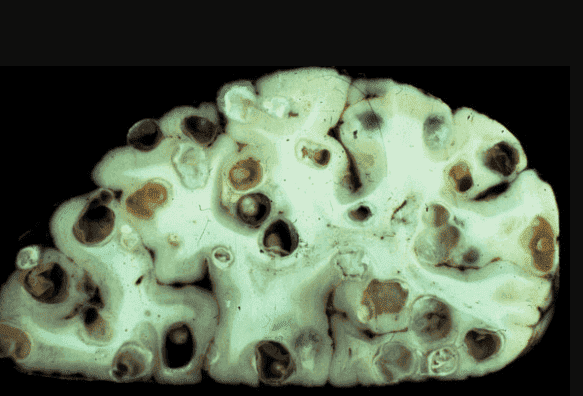

Γιώργος Γαβριηλίδης: Ναι, είναι αλήθεια. Σχεδόν στο 90% των περιπτώσεων, όταν κάνω νεκροτομή, βλέπω μια τρομερή εικόνα. Τα πτώματα είναι γεμάτα με τα παράσιτα! Και τα βλέπω όχι μόνο στον γαστρεντερικό σωλήνα, όπως νομίζουν πολλοί άνθρωποι. Τα παράσιτα ζουν συχνά στους πνεύμονες, στην καρδιά, στο ήπαρ, ακόμη και στον εγκέφαλο! Οι αποικίες τους κατοικούν σε εσωτερικά όργανα και οι προνύμφες τους τρέφονται με τους ιστούς των ζωντανών ανθρώπων!

Μια άλλη περίπτωση: ένας άνδρας 61 ετών. Πέθανε από κίρρωση του ήπατος. Οι συγγενείς του πιστεύουν ότι φταίει το αλκοόλ. Όμως δεν έπινε τόσο πολύ και δεν υπήρχαν ίχνη αλκοολικής καταστροφής του ήπατος, αλλά το ήπαρ απλά έφαγαν από μέσα τα παράσιτα, και βρήκα εκατοντάδες περάσματα μέσα από τα οποία ταξίδευαν τα σκουλήκια.

Άλλη μια περίπτωση που με σόκαρε. Ο εγκέφαλος ενός 49χρονου ασθενούς ήταν γεμάτος με παράσιτα και τις προνύμφες τους. Η αιτία θανάτου ήταν ένα ισχαιμικό εγκεφαλικό επεισόδιο. Αλλά αυτή ήταν μόνο μία από τις συνέπειες! Στην πραγματικότητα, τα παράσιτα απλώς τρέφονταν με τον ανθρώπινο εγκεφαλικό ιστό, τρώγοντάς τον ζωντανό! Καθ' όλη τη διάρκεια της ζωής του, ο ασθενής υπέφερε από πονοκεφάλους, προβλήματα ύπνου και μνήμης. Στη συνέχεια, με πολλές περιοχές ήδη προσβεβλημένες, προστέθηκε και η επιληψία. Έξι μήνες αργότερα, πέθανε.

Ένας εγκέφαλος που έχει προσβληθεί από τα παράσιτα